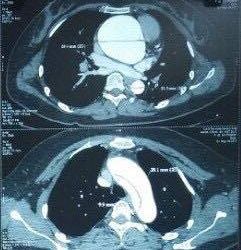

Điển hình là một người bệnh nam giới quốc tịch Sri Lanka. Vốn là một nhân viên tàu viễn dương, mang trong mình bệnh tiểu đường mạn tính, trong những tháng ngày lênh đênh trên biển ông không may xuất hiện các cụm nhọt nhiễm trùng vùng lưng. Vì điều kiện thiếu thốn thuốc men trang thiết bị, tổn thương nhanh chóng lan rộng và tạo thành ổ mủ dọc suốt chiều dài từ lưng xuống tận hông 2 bên. Cũng đúng thời điểm đại dịch Covid-19 đang bao trùm và ảnh hưởng lên cả thế giới, ông và các thủy thủ phải mất 40 ngày mới cập được cảng Quảng Ninh, Việt Nam. Ngay khi đặt chân lên bờ ông đã được đưa đến cơ sở y tế địa phương hội chẩn và sau đó chuyển đến Bệnh viện Hữu nghị Việt Đức điều trị trong tình trạng nhiễm trùng dai dẳng, đường huyết dao động.

Ngày 14/5, người bệnh được được tiến hành hội chẩn và phẫu thuật rạch tháo mủ, cắt lọc làm sạch các ổ nhiễm trùng vùng lưng, đùi cùng với việc kiểm soát đường huyết. Vi khuẩn xét nghiệm là tụ cầu vàng (Staphylococcus Aureus)